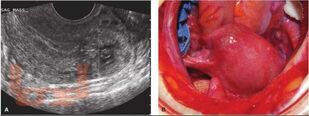

Учебное пособие предназначено для обучения клинических ординаторов согласно учебному плану подготовки кадров высшей квалификации по специальности 31.08.01 «Акушерство и гинекология». В учебном пособии представлены современные сведения об этиологии и патогенезе эктопической беременности, новейших методах диагностики и лечения, в том числе органосохраняющих методиках, как консервативных, так и в сочетании с хирургическими. Подробно рассмотрены различные варианты хирургического лечения эктопической беременности с сохранением репродуктивной функции.